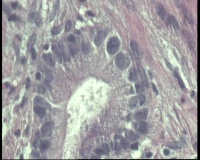

进镜达横结肠近肝曲,见不规则增生性肿物,环周生长,表面充血糜烂,触之易出血,肠腔狭窄,镜身无法通过

镜下腺体异型小,纤维间质反应,能直接报结肠腺癌吗?

可一类报告报:管状绒毛状腺癌

高-中分化腺癌。